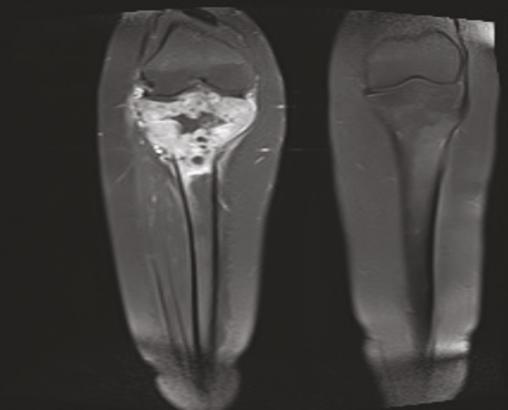

La radiographie standard du genou de face montre une lésion lytique de type géographique excentrée de siège épiphyso-métaphysaire du fémur droit. Elle s’étend sur toute la largeur de l’os, est à contours flous avec une corticale soufflée et rompue, sans réaction périostée ni ossification au sein de la tumeur (fig. 1) . L’imagerie par résonance magnétique (IRM) du genou droit objective une lésion tumorale épiphyso-métaphysaire et diaphysaire de l’extrémité supérieure du tibia infiltrant les parties molles et l’espace articulaire (fig. 2 et 3 ).

Sur le plan morphologique, la radiographie standard permet d’évoquer le diagnostic et de classer la lésion selon les stades de Campanacci. La tomodensitométrie (TDM), quant à elle, joue un rôle essentiel dans le suivi et la recherche de récidives. L’IRM montre un hyposignal T1, signal intermédiaire en T2, à la différence des autres lésions notamment l’abcès et le kyste.